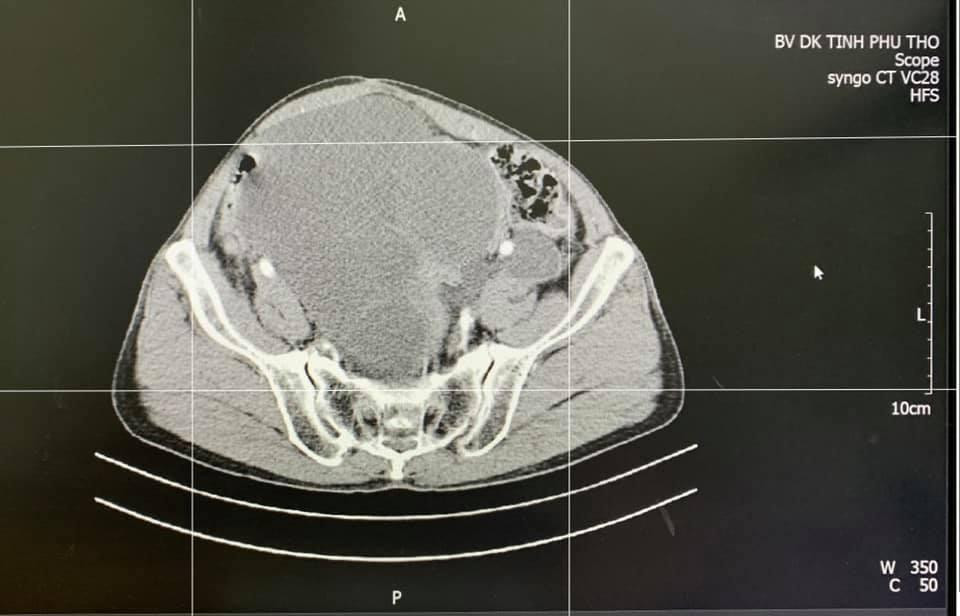

| Khối ung thư phát triển trong cơ thể bệnh nhân. Ảnh: BS cung cấp |